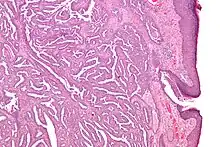

| Micrograph of a nipple adenoma. H&E stain. | |

Once excised, the macroscopic appearance of nipple adenomas is of a poorly defined nodular mass. The microscopic appearance can be quite bizarre, and may be misinterpreted as a carcinoma. Nipple adenomas usually have a rounded outline at low magnification, and at higher magnification can be seen to consist of a haphazardly arranged mass of proliferating tubular structures composed of epithelial and myoepithelial cells within varying amounts of fibrous stroma. The epithelial cells are usually columnar, but the columnar epithelial cells can undergo apocrine or squamous metaplasia. Mitotic figures and necrosis are not commonly seen.[1]